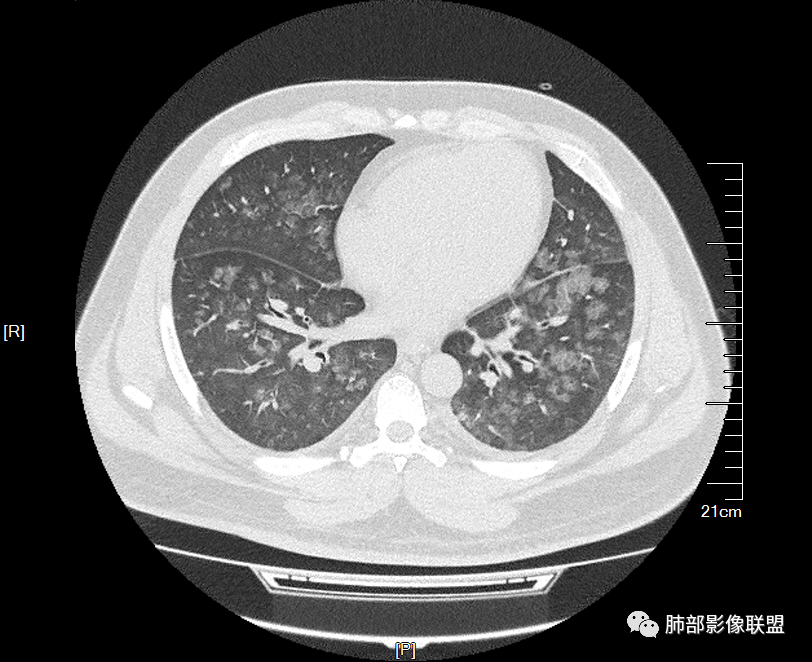

双肺多发弥漫性磨玻璃结节影,大小不一,形态不规则,部分融合,支气管未见明显扩张,部分血管束略增粗,叶裂胸膜增厚,临床有痛风,左足痛6天,考虑:1:痛风结节(一般实性结节,很少磨玻璃结节影)2:血管炎?3:病毒性肺炎(水痘-疱疹肺炎?)

双肺多发腺泡结节及磨玻璃,小叶间隔增厚(大网格状),腺泡结节内及磨玻璃内可见细网格影(小叶内间隔增厚),影像表现符合肺泡出血改变,血肌酐升高,考虑肺肾综合征。鉴别肺水肿。

两肺弥漫向心分布的腺泡结节,部分融合,两肺小叶间隔增厚,血肌肝高,考虑肺泡性肺水肿

年轻男性,既往血肌酐升高,左足痛六天入院,有痛风及高血压病史。CT示双肺多发磨玻璃结节影,不规则,部分融合成团或片状,小叶间隔增厚,以双下肺为明显,叶间胸膜亦见增厚。考虑为1.Good-Pasture综合征。2.病毒性肺炎?3.肺水肿?

男32岁。既往曾发现血肌酐升高.此次因左足痛6天入院。有痛风、高血压病史。两肺弥漫性的病变,小片状或者结节状为主病变,小叶中心分部为主,边界不清。心影比较饱满,肝实质密度均匀的降低。考虑为肝损害的影像学改变。综合考虑多功能脏器的损害,肺部损害肺泡炎?肺水肿?或病毒性的肺炎?

年轻男性,有痛风、高血压病史,有肾功不全史。双肺弥漫性分布磨玻璃样结节,部分融合,无重力分布,考虑1.血管炎。2.肺肾综合征。3.肺水肿。

年轻男性,痛风史,高血压史,肌酐高,左足痛6天入院。胸CT:双肺多发弥漫性磨玻璃结节影,大小不一,部分融合,上中下肺都有,中内带多,胸膜下少。部分血管束略增粗,小叶内间隔、小叶间隔增厚,下肺明显,左室大。叶裂胸膜增厚。临床有痛风,左足痛6天,考虑:心衰、间质性肺水肿?弥漫性肺泡出血?鉴别:MPA,肺肾综合征,痛风结节等。

青年男性,有肾功能不全史和痛风史,这个影像分布有个典型的特点,全部是以中央间质周围的渗出性改变,这个改变主要就是两种可能,一种是肾功能不全导致的血管通透性增高导致的肾性肺水肿,一种是出血导致的DAH改变,具体是哪种,影像上不好简单的鉴别,需要结合更多临床资料综合分析。

年轻男性,痛风,肌酐高,提示肾功能有损,两肺多发磨玻璃腺泡结节,小叶间隔增厚,双侧少许胸水,血管增粗,考虑肾性肺水肿,DAD,鉴别肺肾综合征,需要更多临床资料

双肺多发腺泡结节及斑片状磨玻璃影,边缘不清,后者内见细网格状改变,小叶间隔增厚,呼吸系统症状不明显,考虑肺水肿,过敏性肺泡炎代排

32岁男性,左足痛入院。有痛风、肌酐升高、高血压病史。CT:两肺弥漫磨玻璃结节,小叶间隔增厚、小叶内间质增厚,两侧少量胸水。考虑:1.肺水肿;2.过敏性肺炎;3.肿瘤?

双肺多发腺泡结节及磨玻璃网格影,部分融合,小叶间隔增厚,双肺中轴间质增厚不明显,疾病谱:病毒性肺炎,肺泡出血,水肿,过敏性,肺泡蛋白沉着症,PCP。结合病史,没有咳血,肺泡出血,不考虑,过敏没有任何临床症状,而且无上肺分布优势,也排除。病毒性肺炎也无临床支持,排除。PAP影像不典型,暂排除。有肾功能异常,所以考虑1肾源性肺水肿。2,有无激素使用史或HIV,PCP待排。

青年男性,双肺多发大小不等斑片状磨玻璃密度影,内见细网格影,并可见小叶间隔增厚,双侧胸腔少量积液,患者曾有血肌酐增高,提示曾有肾损害,并有痛风、高血压病史,考虑肺肾综合征,鉴别过敏性肺炎